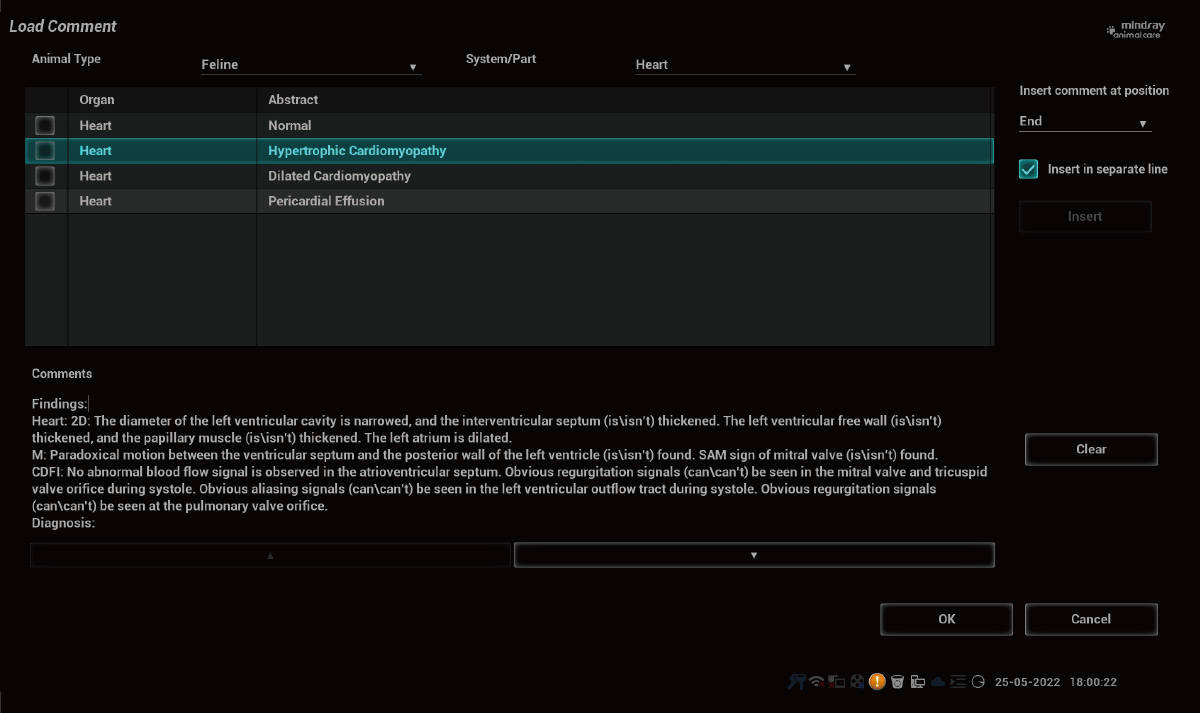

7yo reporto

Proporcione plantillas de informes personalizadas con comentarios profesionales

Indicar condiciones clínicas potenciales o sospechadas inmediatamente.